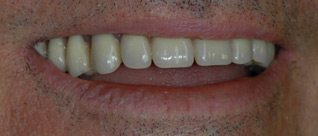

J’ai un appareil amovible du bas que je ne supporte plus, je veux des dents fixées.

Solution : on rajoute autant d’implants que il manque des dents qui serviront à fixer vos nouvelles couronnes.

Mon appareil du haut va bien, mais je voudrais supprimer l’appareil du bas.

Dans ce cas, la prothèse amovible inférieure est supprimée, remplacée par un bridge fixe de 10 dents.